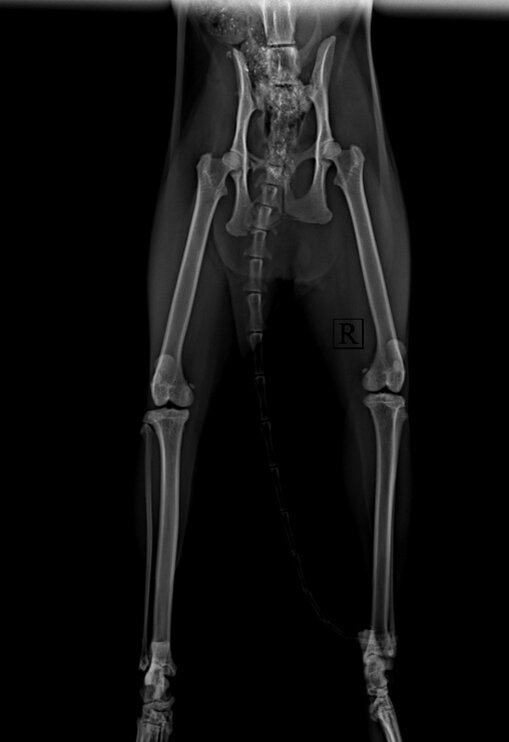

Отрыв крестцово-подвздошного сочленения у кошки.

Знакомьтесь, Мусенька. Кошка попала в ветеринарную клинику в Калуге "Жизнь" с серьезной проблемой. У Мусеньки с помощью рентгена диагностировали отрыв крестцово-подвздошного сочленения.

Кошке провели полное предоперационное обследование, наши специалисты разработали план операции, подобрали для кошки наркоз и провели сложную ортопедическую операцию - стабилизацию крестцово-подвздошного сочленения.

Операция прошла в штатном режиме, Мусенька полностью вышла из наркоза на стационаре, после чего ее забрали домой. Сейчас кошка отлично себя чувствует и смело бегает!

Кошка после осмотра ветеринарного врача ортопеда Турковой Татьяны Григорьевны в ветеринарной клинике в Калуге "Жизнь".